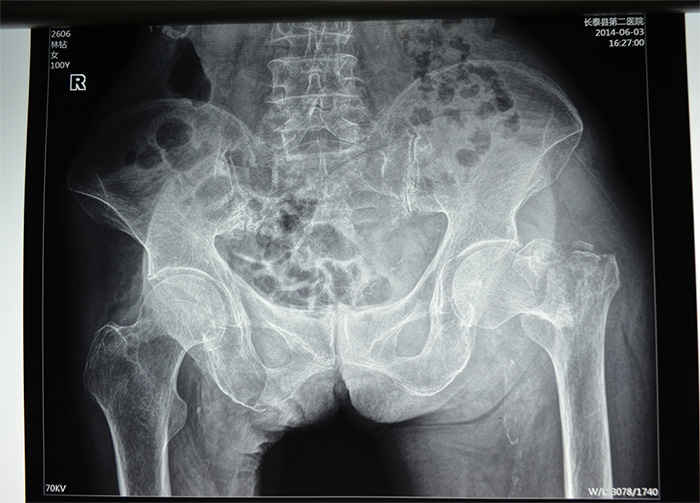

据家属介绍,百岁老人身体还不错,平时生活能自理,还能做家务。5月20日上午,她在洗衣服的时候,由于地面湿滑,摔倒在地,当时左腿就无法站立,送到当地医院拍片,发现左腿髋部骨折严重,且错位明显。考虑患者高龄,骨折严重,手术风险高,技术难度大,当地医院无法完成手术,转入厦门第三医院治疗。

林老太入三院时,左腿的髋部骨折处已翻转90度,还出现短缩移位,左腿比右腿短了5—6公分。由于疼痛,每次大小便,对老人来说都是一次折磨,她也不敢正常摄入食物,导致出现低蛋白,且原先就有高血压的症状,心血管功能比较差,手术风险极高,如果采用传统的骨折开放复位钢板固定术,对于高龄特别是骨质疏松患者,手术失败率很高,同时卧床时间长达三四个月,极易引发并发症。骨科主任刘忠国说。

老人应选择何种治疗方案?第三医院骨科、心内科、麻醉科等多科专家组成的专家组认真仔细分析病情,决定采用髋关节微创植入内固定术。6月4日,老人接受手术,在手术牵引床上,通过C臂X光机透视,不切开骨折端闭合牵引复位,在老人骨折处复位到最佳状态时,刘忠国在骨折处开出5公分的口进行螺旋刀片动力髋固定,最大程度减少手术损伤,促进骨折端提早愈合。